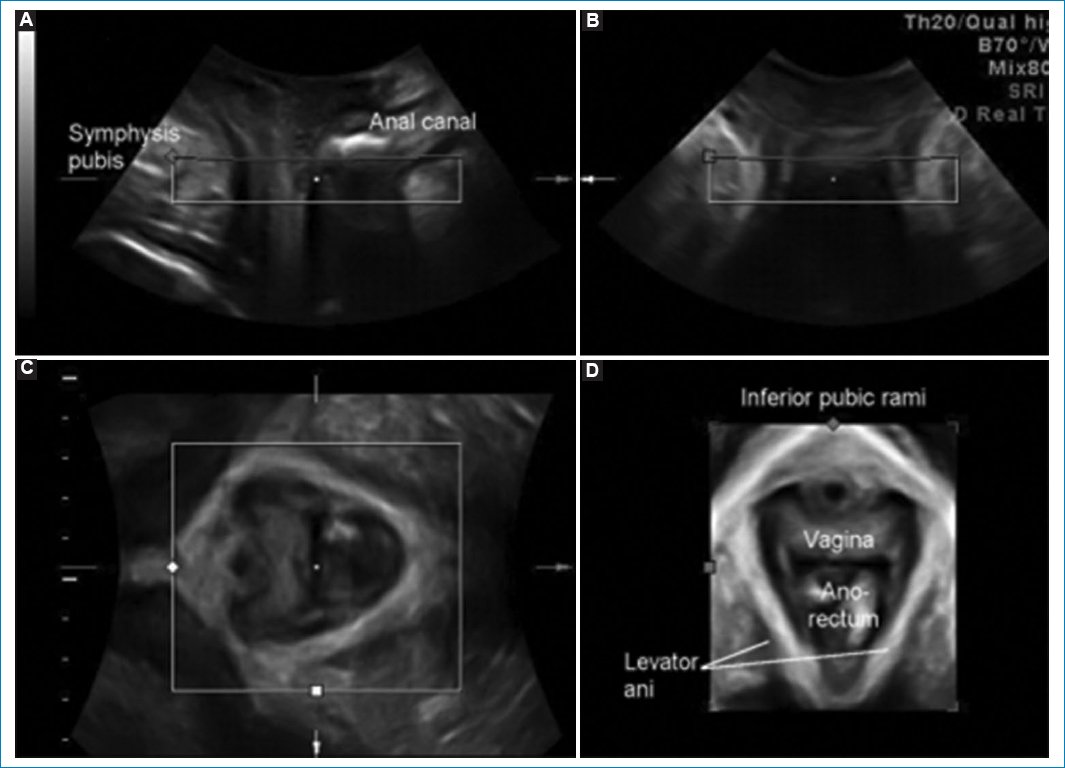

Figura 17. (A-D) Se observa la anatomia normal del plano axial pelviano reconstruido en 3D.

Plano axial 3D-4D7 (Fig. 17)

• – Integridad del haz puborrectal: se evalúa en contracción máxima y se reconstruye en 3D y 4D, se cuantifica el grado de lesión con el ultrasonido tomográfico (Fig. 18).

• – Avulsión del haz puborrectal unilateral o bilateral: la distancia entre la uretra y el músculo puborrectal bilateral no debe ser mayor a 25 mm. Unilateral: asimetría.

• – Microtraumas del elevador del ano: balonización del hiato urogenital en Valsalva. El balonamiento del hiato urogenital se considera cuando es mayor a 25 cc, esto se asocia con prolapso y síntomas de prolapso y mayor probabilidad de recurrencia en reparaciones de rectoceles (Fig. 19).